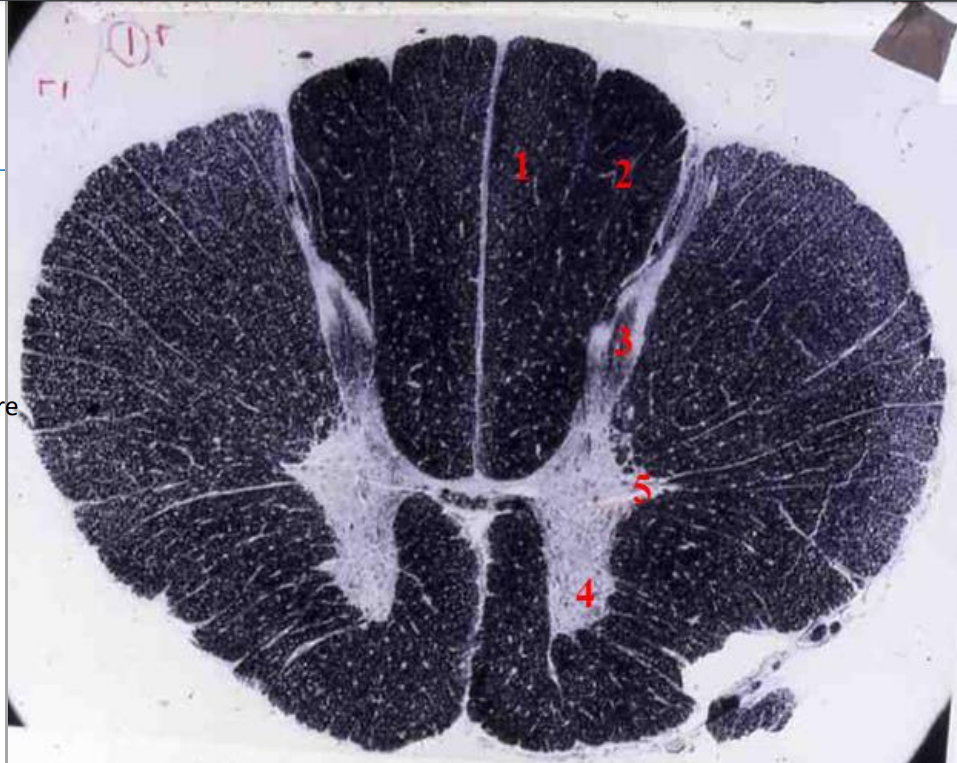

Q

indentify the weigert

A

cervical cord

- fibre tracts are larger

- grey matter is large

- brachial plexus

- no lateral horn

12

1

fasiculus gracilis

13

2

fasciculus cuneatus

14

3

posterior horn

15

4

anterior horn